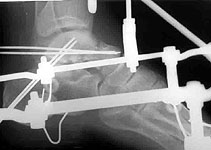

I want to submit a case. A patient after car accident (was inside) got multiple injuries. The question focused on his talar neck and facet fracture which can be seen below.

The lateral view of this foot shows a talar neck fracture with at least 1 cm of displacement as well as a significant luxation of the posterior subtalar joint. In my opinion, if soft parts are OK, this case would require open reduction and internal fixation.

This is a displaced fracture with some crush element to the neck region as well as a subluxation of the posterior facet. It will be difficult to reduce through anything other than simultaneous medial and lateral approaches. It will probably require plate fixation rather than lag screw fixation to maintain the facet relationships. A CT scan would be helpful in determining if you have to go through the whole exercise or do something more minimal.

About the foot - its plantar flexion helped to reduce the subluxation. The neck looked also more attractive in this position. So i fixed it with two pair of wires - a couple from posterolateral side to the neck, another pair - through calcaneus and posterior facet - without the wires it would be needed to fix the foot in maximal equinus to prevent subluxation recurrence. Depressed part of the anterior facet stayed in place :-(

Postop Xray is attached. Sorry, axial view is of poor quality.